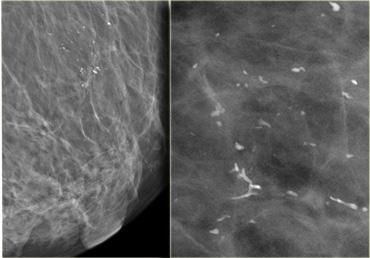

Hầu hết các vôi hóa trong tuyến vú hình thành bên trong các ống tận cùng (vôi hóa trong ống) hoặc bên trong các nang tuyến (vôi hóa tiểu thùy).

TRÁI: Vôi hóa tiểu thùy: dạng chấm, tròn hoặc ‘sữa canxi’ (milk of calcium). PHẢI: Vôi hóa trong ống: đa hình thái và tạo thành khuôn đúc theo phân bố tuyến tính hoặc phân nhánh.

Vôi hóa tiểu thùy

Các vôi hóa này lấp đầy các nang tuyến, thường ở trạng thái giãn rộng.

Kết quả là tạo ra các vôi hóa đồng nhất, thuần nhất và có bờ viền rõ nét, thường có dạng chấm hoặc tròn.

Vôi hóa trong ống

Các vôi hóa này là các mảnh vụn tế bào hoặc chất tiết đã bị vôi hóa nằm trong lòng ống tuyến.

Sự vôi hóa không đều của các mảnh vụn tế bào lý giải cho tình trạng phân mảnh và bờ viền không đều của các vôi hóa.

Các vôi hóa này cực kỳ đa dạng về kích thước, tỷ trọng và hình dạng (tức là đa hình thái, từ tiếng Hy Lạp pleion ‘nhiều hơn’ và morphe ‘hình dạng’).

Đôi khi chúng tạo thành khuôn đúc hoàn chỉnh của lòng ống tuyến.

Điều này lý giải tại sao chúng thường có dạng và phân bố tuyến tính mảnh hoặc phân nhánh.